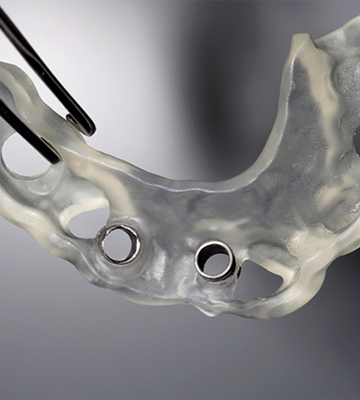

En CAD Dental Innovations nos especializamos en el diseño y fabricación de prótesis dentales personalizadas, combinando precisión, funcionalidad y estética. Utilizamos las últimas tecnologías digitales del sector —como Exocad, 3Shape y Blender for Dental— para ofrecer soluciones adaptadas a las necesidades específicas de cada caso clínico.

En CAD Dental Innovations, nuestra pasión es transformar sonrisas y mejorar vidas a través de la tecnología de vanguardia y la artesanía dental de alta calidad. Somos un laboratorio especializado en prótesis dentales digitales, comprometido con ofrecer soluciones innovadoras y personalizadas.

Desarrollamos archivos 3D para prótesis dentales con la máxima precisión. Desde el escaneo hasta la fabricación, optimizamos cada fase del proceso para garantizar soluciones a medida y adaptadas a las necesidades de cada paciente.